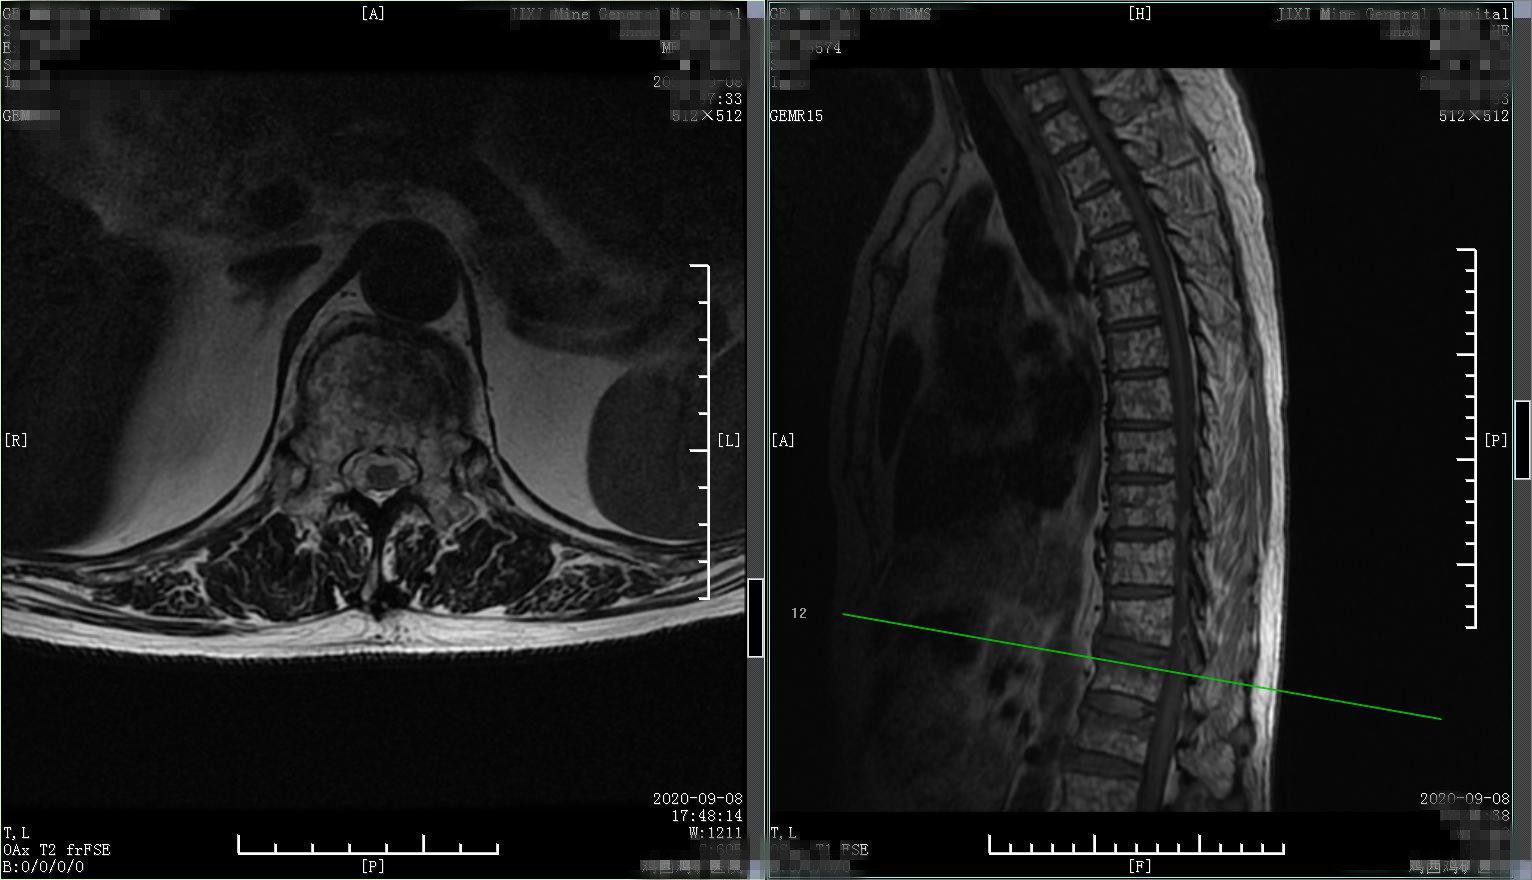

患者2,患者老年女性,80岁,慢性腰背部疼痛多年,程度轻,对日常生活无明显影响,平时可生活自理。就诊前2个月开始腰背部疼痛加重,偶尔夜间能疼痛,口服止痛药物疼痛可减轻,自认为腰椎间盘突出、骨质增生所致,采取针灸治疗半月余,无任何改善,又前往个体中医门诊外敷膏药治疗,疼痛进行加重,并出现因疼痛严重导致翻身困难,于就诊前一周开始出现双下肢麻木、双腿活动不灵活、无力,无法下床站立、行走,逐渐出现大小便*禁失**,就诊时已进展为双下肢截瘫。查腰椎X线片,可见脊柱侧弯、骨质疏松、椎体前缘由变扁。病人出现脊髓损害,进一步查核磁,结果如下:

核磁表现为 脊柱转移瘤 ,肿瘤长入椎管压迫脊髓,所以导致病人出现截瘫。经完善检查病人确诊为脊柱转移瘤、胸脊髓损害,因一般状态进行性恶化,约1个月后患者死亡。